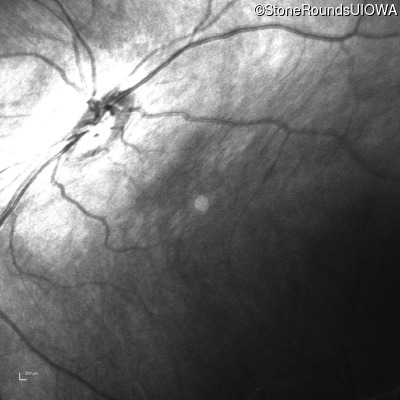

Infrared Fundus Photograph - Right - 20/80

Exemplar